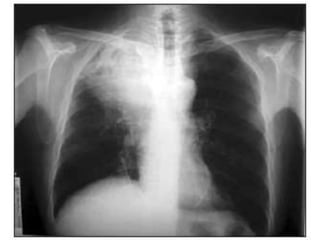

Clinica

SEPAR 2009

DIAGNOSTICO